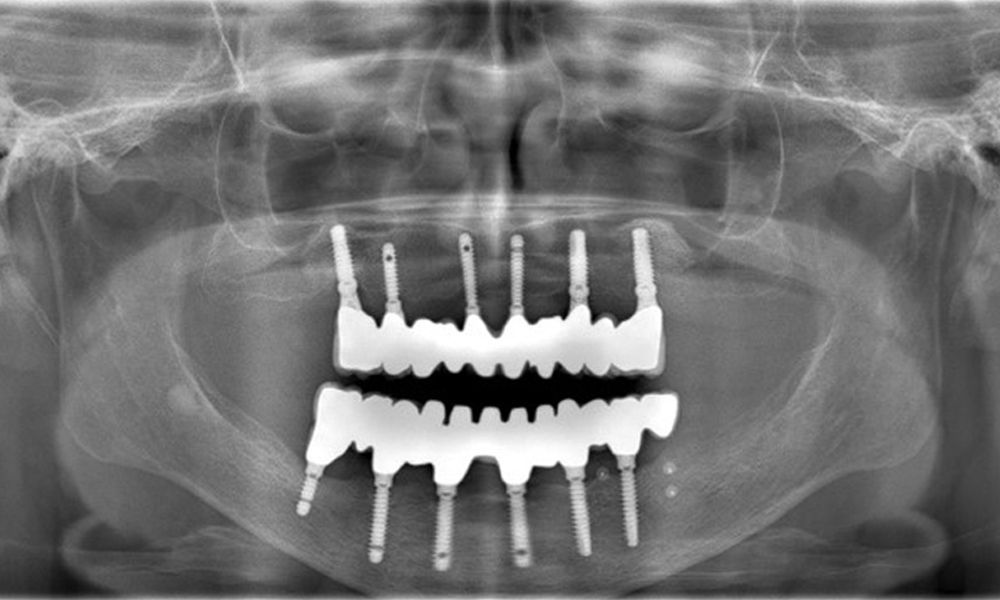

Die Röntgenaufnahmen zeigen den Knochenabbau.

Abb. 2: Die Röntgenaufnahmen zeigen den Knochenabbau.

Eine 74-jährige Patientin stellt sich in der Sprechstunde vor. Die Anamnese zeigt, dass die Patientin gut eingestellten Bluthochdruck hat und Lixiana einnimmt. Weiterhin hatte die Patientin im Jahr 2020 ein Nierenkarzinom. Die Lebensgewohnheiten der Patientin sind unauffällig. Die Patientin hat keine eigenen Zähne mehr. Sie hat im Oberkiefer und Unterkiefer jeweils sechs Implantate, die mit Kronen bzw. über Brücken versorgt sind. Anhand der aktuellen Befunde lässt sich keine periimplantäre Mukositis bzw. Periimplantitis feststellen; vereinzelte (geringfügige) Blutungen an den Implantat(-versorgungen) liegen vor.

Versorgungen: Implantate regio 011, 013, 015, 021, 023, 025, 031, 033, 035, 042, 044, 046

Ein Risikofaktor stellt die Einnahme von Lixiana dar; dementsprechend ist das Komplikationsrisiko als moderat zu bewerten. Es zeigt sich eine gute, stabile Mundgesundheit. Um frühzeitig auf eine potenzielle Periimplantitis aufmerksam zu werden, sollten während der Kontrolltermine die Sondierungstiefen (ST) gemessen werden. Zeigt sich am Implantat eine Vergrößerung von ST im Vergleich zur Baseline, kombiniert mit einer diffusen Blutung, so sollte eine Röntgendiagnostik (i. S. eines Zahnfilms) angestrebt werden.